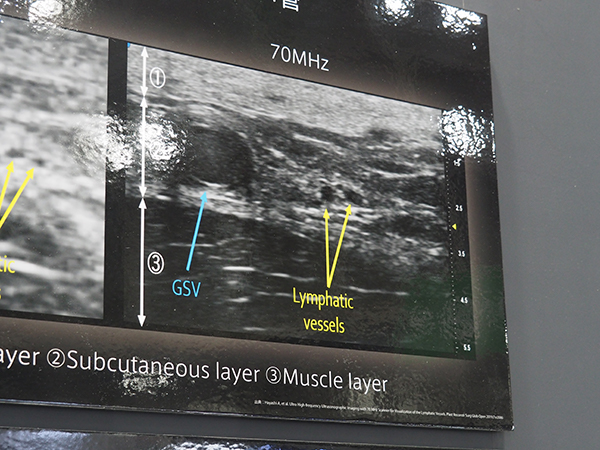

超音波診断装置では,70MHzの超高周波プローブを搭載した超高周波超音波画像診断装置「SonoSite Vevo MD」を先行出展した。米国では2016年にFDAの承認を受け販売を開始し,国内でも研究用途向けで販売されていたが,今回,臨床向けとしてITEMで先行展示を行った。SonoSite Vevo MDは,70MHzと48MHzの超高周波プローブを利用でき,70MHzでは最小分解能30μmの超高精細画像が取得できる。これによって,表在の血管やリンパ管など従来の超音波診断装置では描出が難しかった組織の描出が可能で,形成外科領域などでの活用が期待される。

70MHz超高周波プローブでは大伏在静脈やリンパ管などの描出が可能